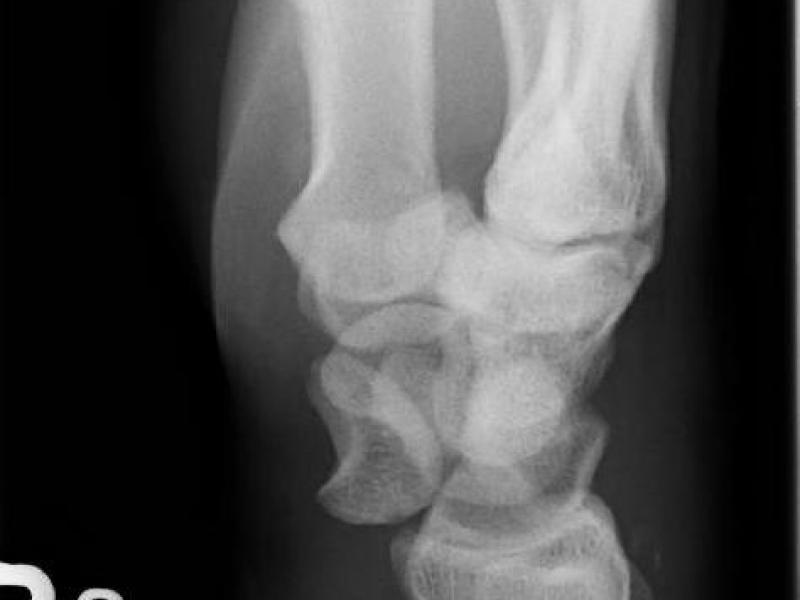

Back to Basics: Lunate vs Perilunate Dislocation

Back to Basics: Lunate vs Perilunate Dislocation By: Angela